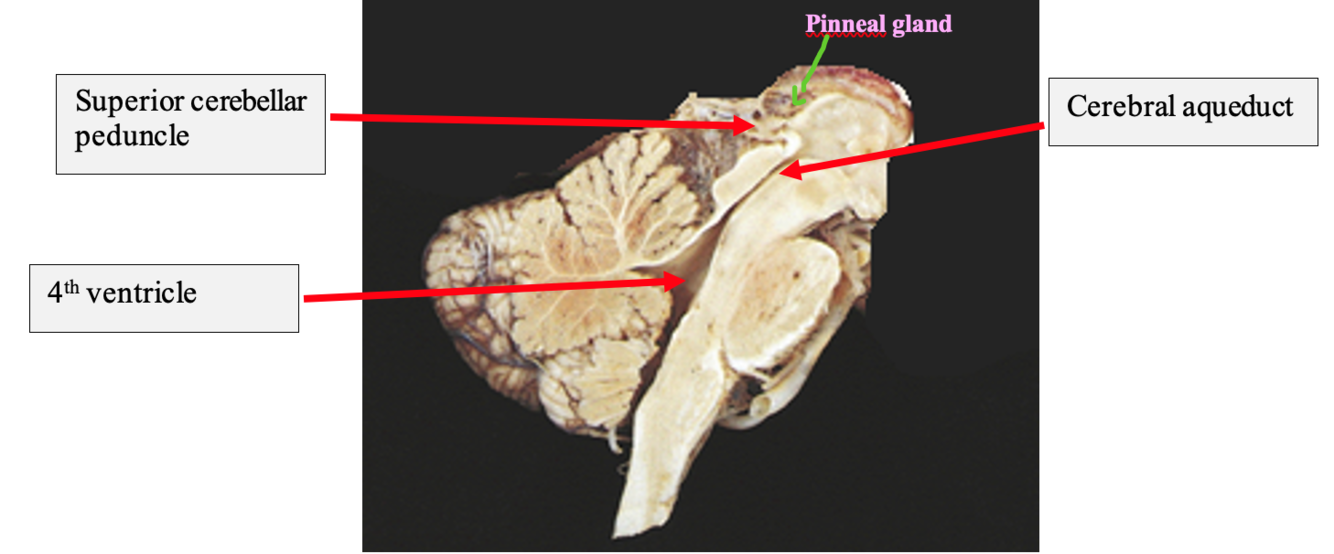

Name this gland

The pinneal gland- part of the epithalamus, posterior to the thalamus